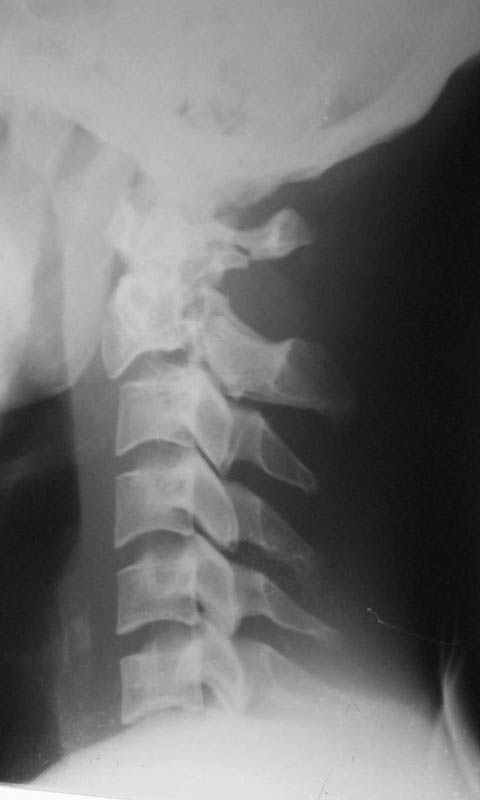

At our centre: Haemodynamically stable. Grade III compound fracture left femur with a wound anteromedially in the middle thigh through which the femur had come out. Distal pulse present. Cervical spine - C1 post ring fracture right side. C2 fracture body with listhesis. No canal compromise. No neurological deficits clinically.

X rays and CT film attached. We have put the patient on skull traction and posted him for debridement and proceed ----. What we have done I would like to present after the discussion.